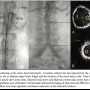

In preparation for the endovascular procedure, a computerized tomography (CT) angiogram of the abdominal aorta and iliacs was performed on an outpatient basis, which verified absence of aortic aneurysm and allowed for precise measurement of aortic lumen dimensions at proximal and distal reference sites as well as at the target lesion, and also of distance between target lesion and both renal arteries (Figures 1A and 1B and Figures 2A–2D). Based on this information, the infrarenal aortic procedure was planned with use of a balloon-expandable 10-mm diameter stent with plans to postdilate with a 12 mm balloon. Both devices could be delivered via a 7 Fr sheath. The bilateral ostial iliac stenosis precluded the use of larger-sized sheaths.

After ascertaining left and right common femoral artery access, aortography was performed and a 20 MHz intravascular ultrasound imaging catheter was used over a 0.014˝ support wire in order to further assess the infrarenal aorta and the left common iliac artery stenosis (the left side was selected, since less obstructive and calcified than the right common iliac). Important measurements with these 2 imaging modalities as well as key angiographic images are shown in the Table and also in Figures 1 and 2 in correlation with the respective tomographic measurements that were utilized for device sizing.

Following removal of the balloon catheters, a marker 5 Fr pigtail catheter was advanced to the level of the renal arteries from the right side, while the dilator was reinserted in the left side sheath, which was subsequently advanced across the infrarenal aortic stenosis, which was ~75% obstructive angiographically. The dilator was then exchanged for a 10 x 37 mm balloon-expandable stent and the sheath was retracted in order to uncover the stent in position. Guiding angiography from the marker catheter was used (Figure 3, left panel) to avoid stent deployment across the renal arteries, and then the diagnostic catheter was withdrawn. The stent was deployed with one inflation at 10 atm and subsequently postdilated at 14 atm with a 10 x 12 mm balloon, resulting in excellent angiographic and ultrasound results (Figure 3). The thoracic aorta to femoral pressure gradients were eliminated bilaterally.